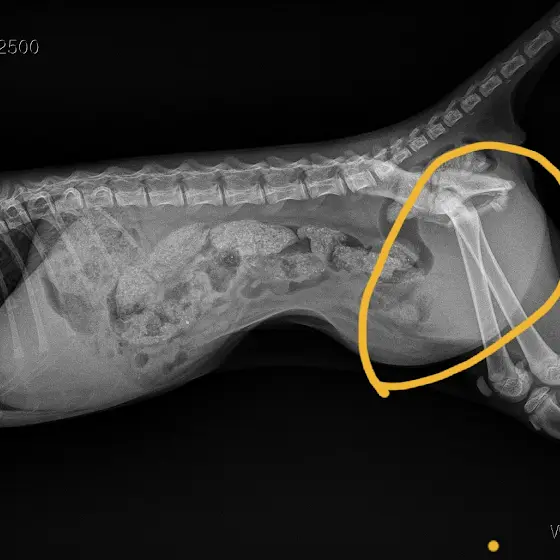

✔️ 부산 사상에서 운전해서 도로를 달리던 차안에 있던 아기고양이가 미처 못나오고있다가 달리는중 나오려하면서

골반골절과 방광 탈장이 일어난것같고,

✅️ 방광탈장수술, 골반골절 수술비 마련이 시급합니다 ✅️